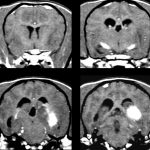

2017年8月15日 / 最終更新日 : 2025年6月27日 武内どうぶつ病院 症例報告 犬の脳炎について(NME, NLE, GMEなど) 犬の脳炎には4つの代表的な疾患があります。最近とくに、「犬の脳炎」が増えているように感じています。 ●犬ジステンパー脳炎 (CDVE) ジステンパーウィルスによって引き起こされると言われています。大脳、脳幹、小脳、脊 […]